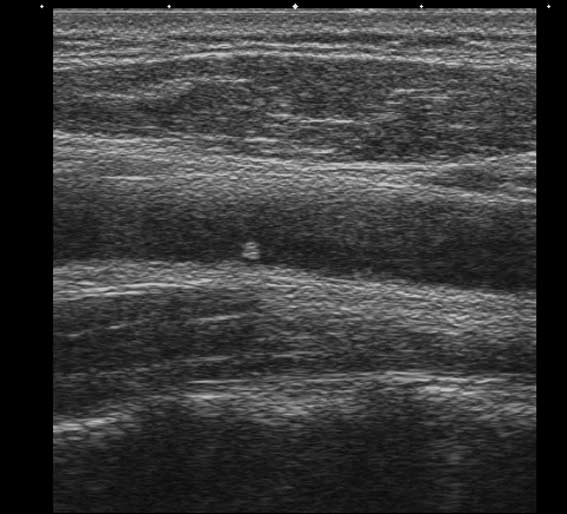

мужчина, 49 лет, при обследовании БЦА в общей сонной артерии визуализируется округлое образование 1.7х2.0 мм

ваше мнение?

Кальцинированная атеросклеротическая бляшка. Для уточнения ее истинного размера примените энергетический доплер.

локальная атеросклеротическая бяшка, которая не вызовет гемодинамически значимых изменений(если оценивать бляшку только в продольном сечении)